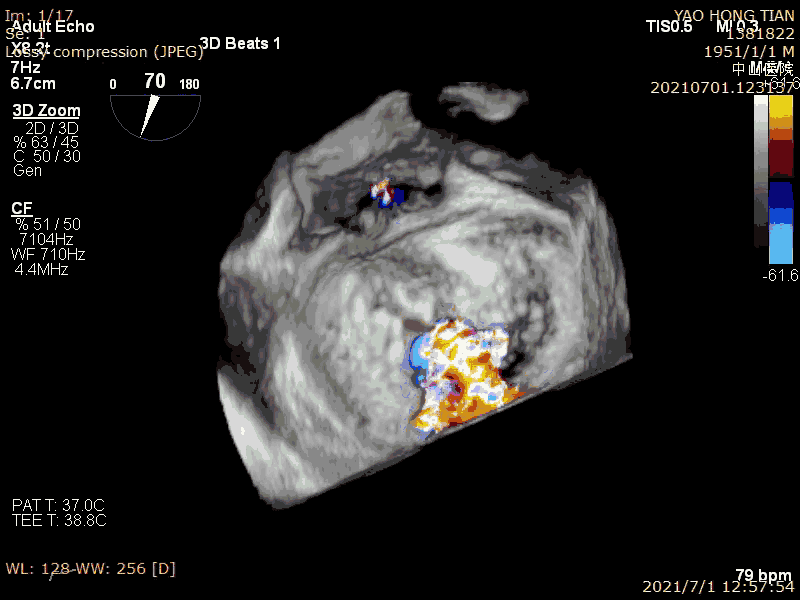

最后效果(轻微反流),最大/平均压:差4/1mmHg

在二尖瓣反流病因构成中,功能性反流更常见,其为器质性反流的3-4倍(Am Heart J. 2018 ;203:39-48.)。而房性功能性二尖瓣反流(AFMR),在功能性反流里也是非常常见,笔者估测可占到40%。本例结果显示ValveClamp 对AFMR效果良好,操作简便,导管操作时间不到20分钟,总手术时间不到50分钟,术后轻微反流。特别提到的是,本例反流范围达13mm,且反流为多束。一个夹子ValveClamp即起到完美效果,而其他产品很可能需要2-3个夹子,这充分体现了ValveClamp“以小治大” 的设计优点。仅使用单个夹子,可以降低手术难度和手术时间,降低耗材成本。